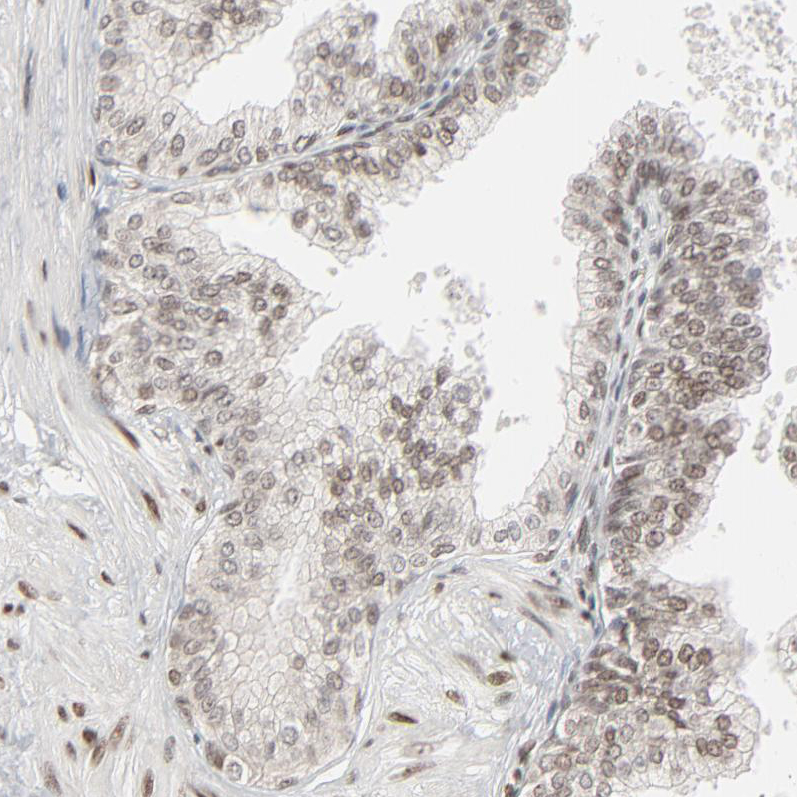

Immunohistochemical staining of human cerebellum shows strong nuclear positivity in all layers.